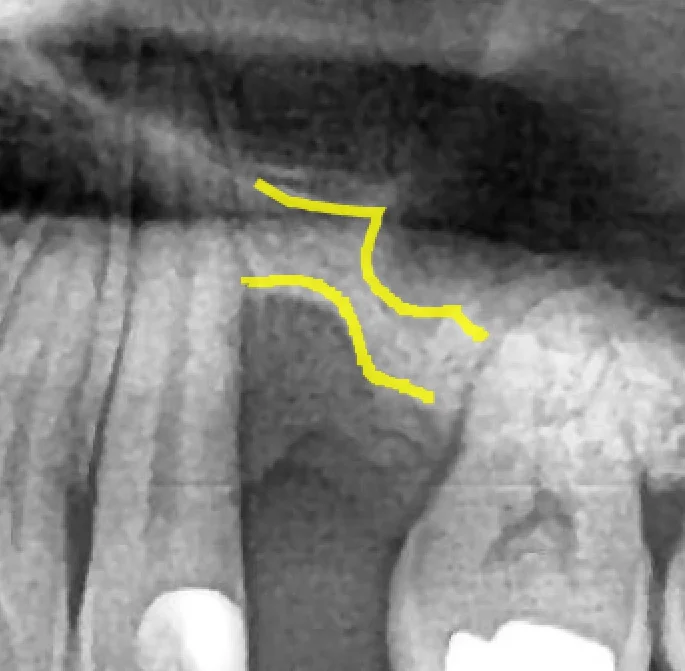

임플란트 뼈이식 – 뼈가 부족해도 가능한 3가지 방법 | 파주 서울이고운치과

임플란트 뼈이식 수술 전후 파노라마 비교 - 상악동 거상술과 GBR 동시 시행

“뼈가 부족해서 임플란트가 어렵습니다.” 이 말을 듣고 치료를 포기하신 분들이 적지 않습니다. 하지만 임플란트 뼈이식을 통해 부족한 뼈를 보충하면, 대부분의 경우 임플란트 식립이 가능합니다. 국제 학술 연구에 따르면 뼈이식 후 임플란트 생존율은 평균 98.5%(PMC Systematic Review)에 달합니다. 중요한 것은 포기가 아니라, 정확한 진단과 적절한 수술 계획입니다. 왜 뼈가 부족해지나요? — 임플란트 뼈이식이 필요한 3가지 상황 … Read more